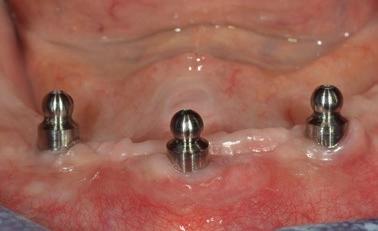

Ce module a pour objectif de vous permettre de diagnostiquer, planifier et réaliser des restaurations complètes fixes et amovibles sur implants, que ce soit sur barre ou à l’aide d’attaches individuelles. Il s’adresse aux professionnels souhaitant approfondir leur compréhension des options de traitement en édentation complète, partielle ou en dentition terminale.

Vous apprendrez à distinguer les différents profils cliniques, à reconnaître les indications et limites des diverses restaurations (mandibule et maxillaire), et à orienter vos patients vers des solutions adaptées à leurs besoins et attentes.

Tout au long de la formation, vous profiterez de l’expertise développée au Centre à travers plus de 3 500 cas d’édentation complète traités et aurez l’occasion d’observer en direct les étapes chirurgicales et prothétiques, que ce soit en salle ou via une retransmission depuis la salle de cours.

Nombre et position des implants selon le type de restauration (fixe/amovible, barre/attaches)

Prothèses complètes sur attaches individuelles

Prothèses partielles amovibles sur attaches (ex. : LOCATOR / NOVALOC)

Sélection et utilisation des piliers (UNI, Atlantis, boule, LOCATOR, NOVALOC…)

Choix du système d’attaches selon le cas